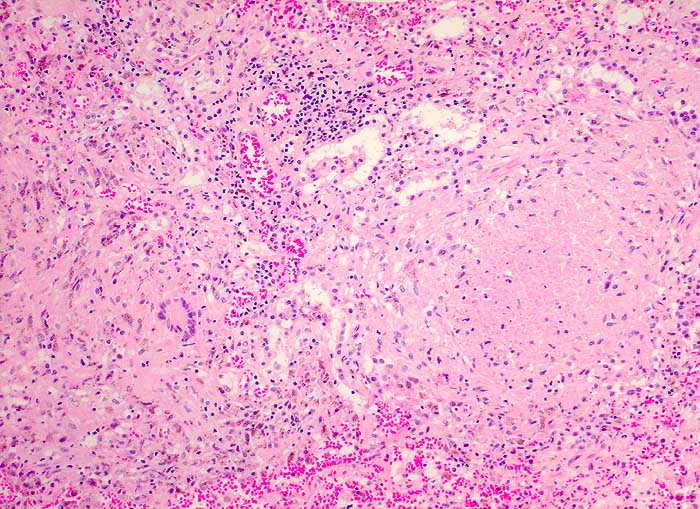

Die meist atrophischen Epitheloidzellen sind oft nur schwer von Venulenendothelien unterscheidbar und sind nur relativ selten zu deutlich erkennbaren Granulomen zusammengeballt. Bei Vorliegen von verkäsenden Granulomen erscheint der Ausstrich feinkörnig-detritisch. Eine granulozytäre Entzündung muss bei AIDS Patienten an eine Tuberkulose denken lassen.